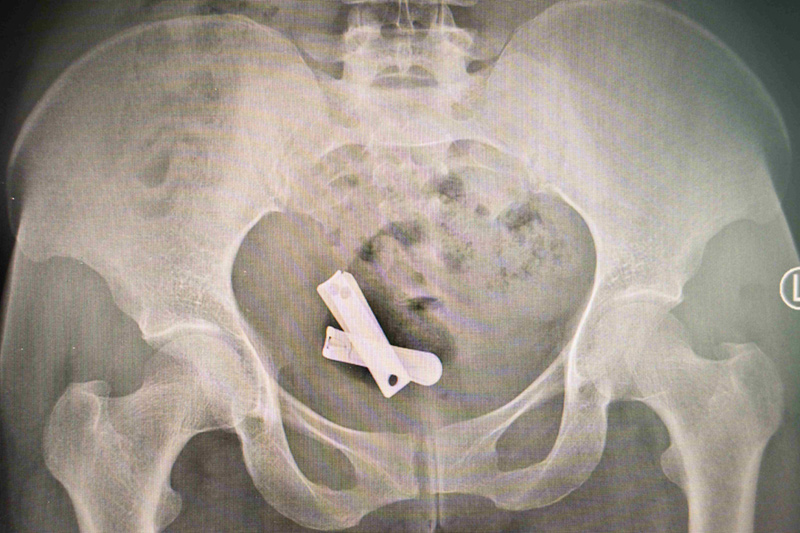

The presentation turns to the Tigray region in northern Ethiopia. Following an escalation between the Ethiopian central government and the Tigray People’s Liberation Front on 4 November 2020, the conflict has been described by multiple observers as among the bloodiest of the twenty first century. Referencing findings cited by legal and human rights organisations, María Ximena outlines the reported toll over two years, including large scale displacement, widespread killings, and the systematic use of sexual violence. Throughout, she foregrounds survivor dignity, verification, and the responsibilities of visual journalists working in highly sensitive contexts.